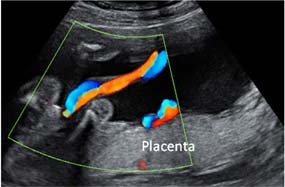

Cómo se hace el estudio Doppler en una gestación múltiple

El estudio Doppler se realiza mediante una ecografía y consiste en estudiar el flujo sanguíneo de los vasos fetales. Se puede estudiar la circulación entre el feto y la placenta (fetoplacentaria) mediante la medición del Doppler en la arteria y la vena umbilical; o se puede estudiar la circulación fetal mediante la medición de la arteria cerebral. Esta prueba permite detectar precozmente, mucho antes que el registro y la medición de líquido amniótico, aquellos bebés que pueden estar sufriendo dentro del útero. Actualmente se suele realizar un estudio Doppler en cada ecografía a la que acudas, de forma complementaria a la medición de los dos fetos. Teniendo un estudio Doppler normal de los dos bebés, puedes quedarte muy tranquila. Esta prueba actualmente ha desplazado al perfil biofísico, aunque en algunos centros lo siguen realizando.